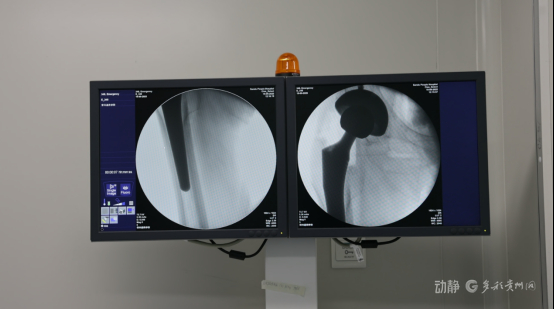

近日,黔南州三都县人民医院(医共体)总院在中组部医疗人才“组团式”帮扶专家团队的指导下,成功完成县域首例高难度髋关节翻修手术,标志着该县骨科诊疗水平实现重要突破。

手术由中组部“组团式”帮扶专家、遵义医科大学附属医院骨科副主任吴术红全程指导。术前,团队通过三维CT等影像技术精准评估假体位置及骨缺损情况,制定个性化方案;术中,专家团队凭借丰富经验,顺利完成髋臼及股骨侧假体取出、植骨填充及新假体精准安装,手术出血量少、耗时短于预期。术后,患者生命体征平稳,疼痛显著缓解,次日即可在助行器辅助下下地行走,恢复效果远超预期。